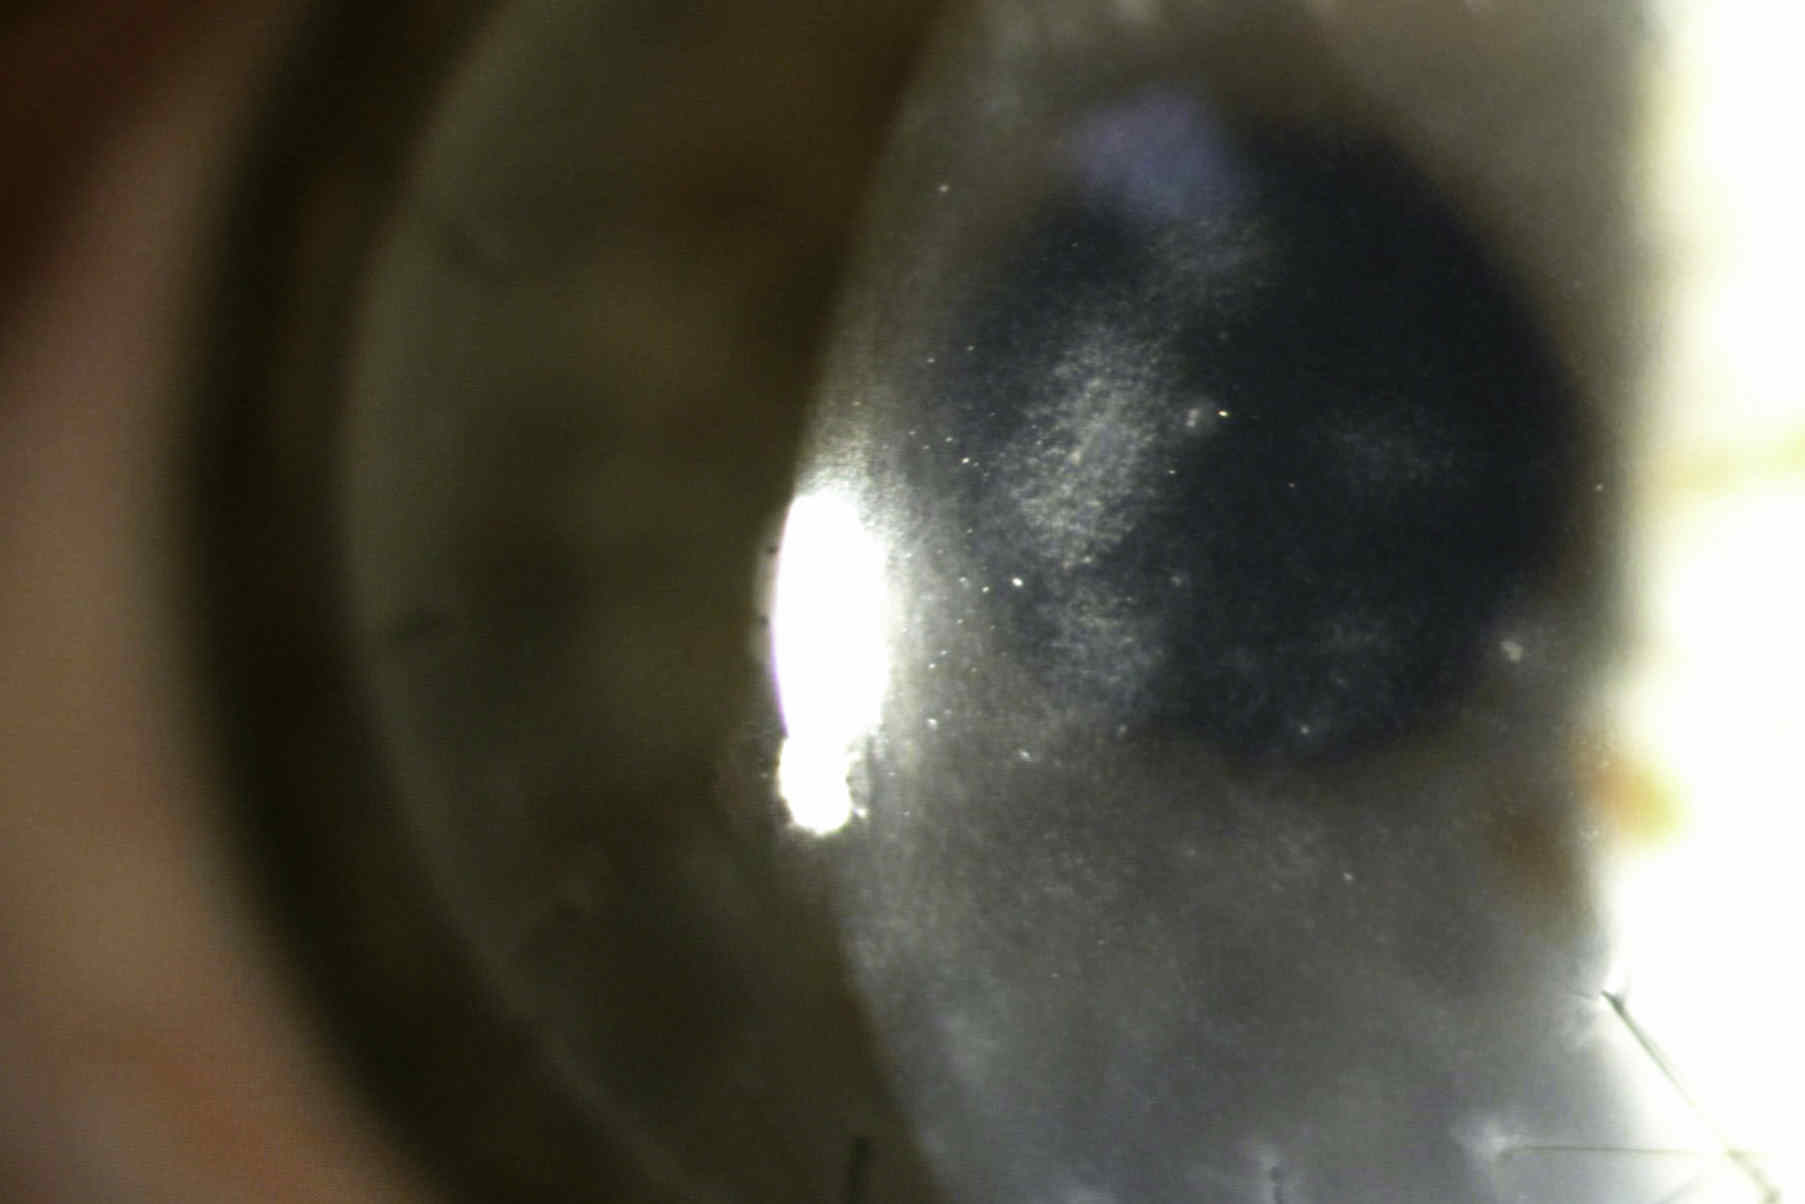

Case study: There was an old lady who fly sprayed her eye…

A peculiar case of corneal oedema in an elderly patient, highlighting the importance of obtaining collateral history when there’s no obvious cause.